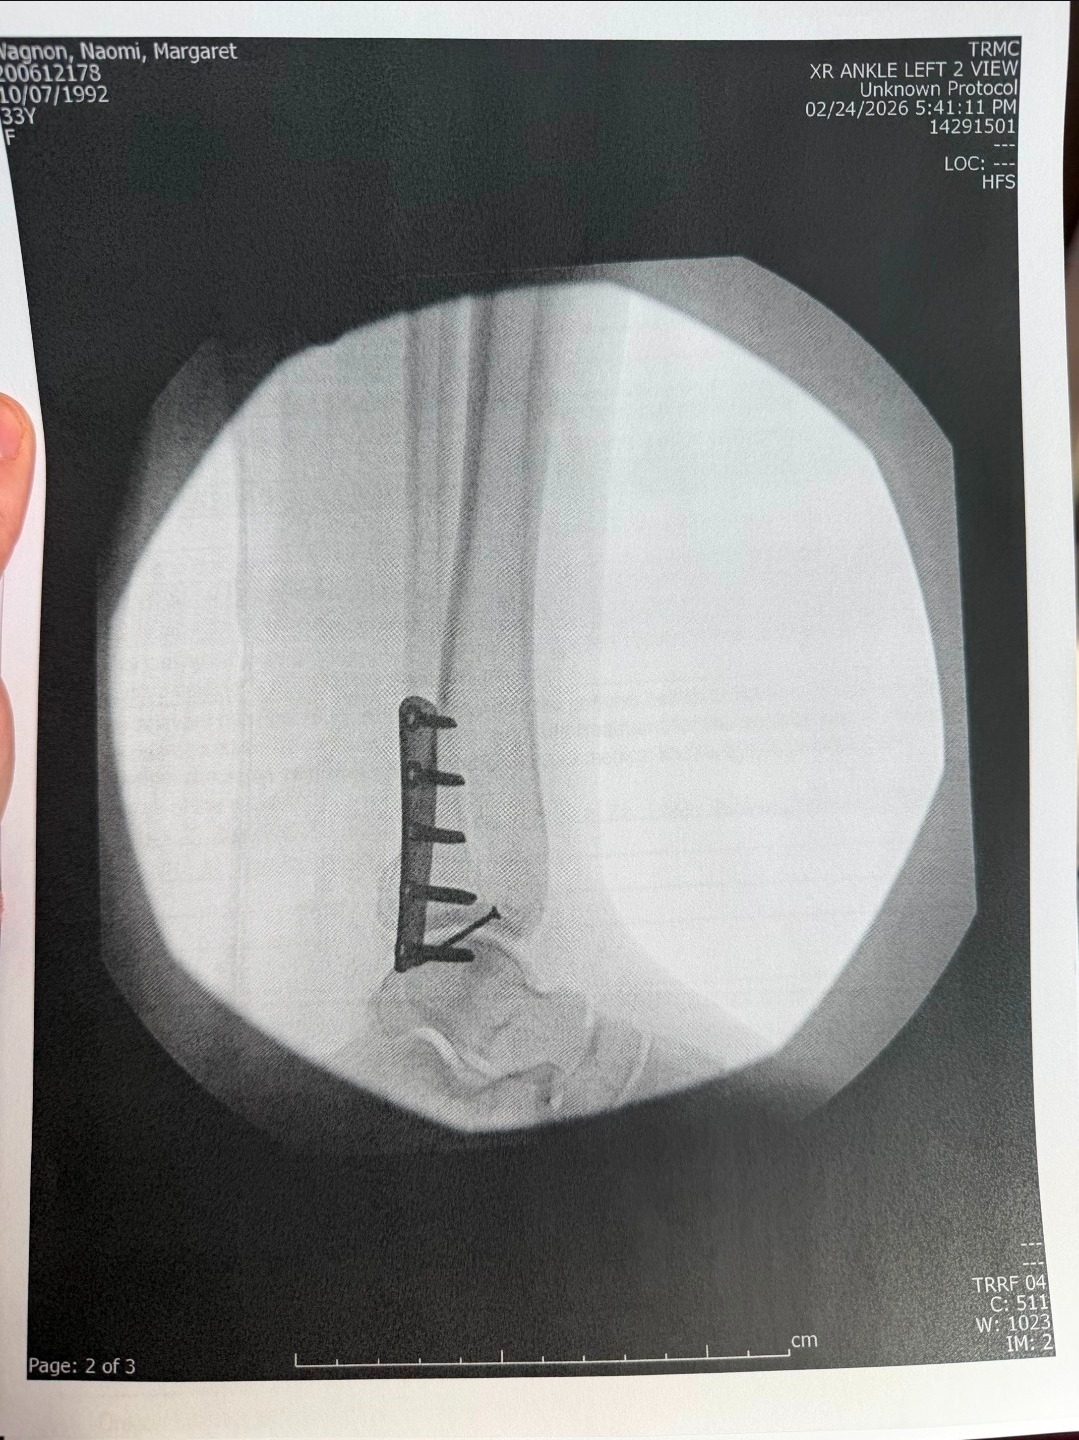

During the first significant snowfall in southern Oregon, Naomi slipped on her front steps and suffered a severe injury—breaking her ankle in multiple places, tearing tendons, and dislocating the joint. She underwent surgery within a week and is now on the long road to recovery. As a mother, it’s heartbreaking to see her in pain and facing so many challenges all at once.